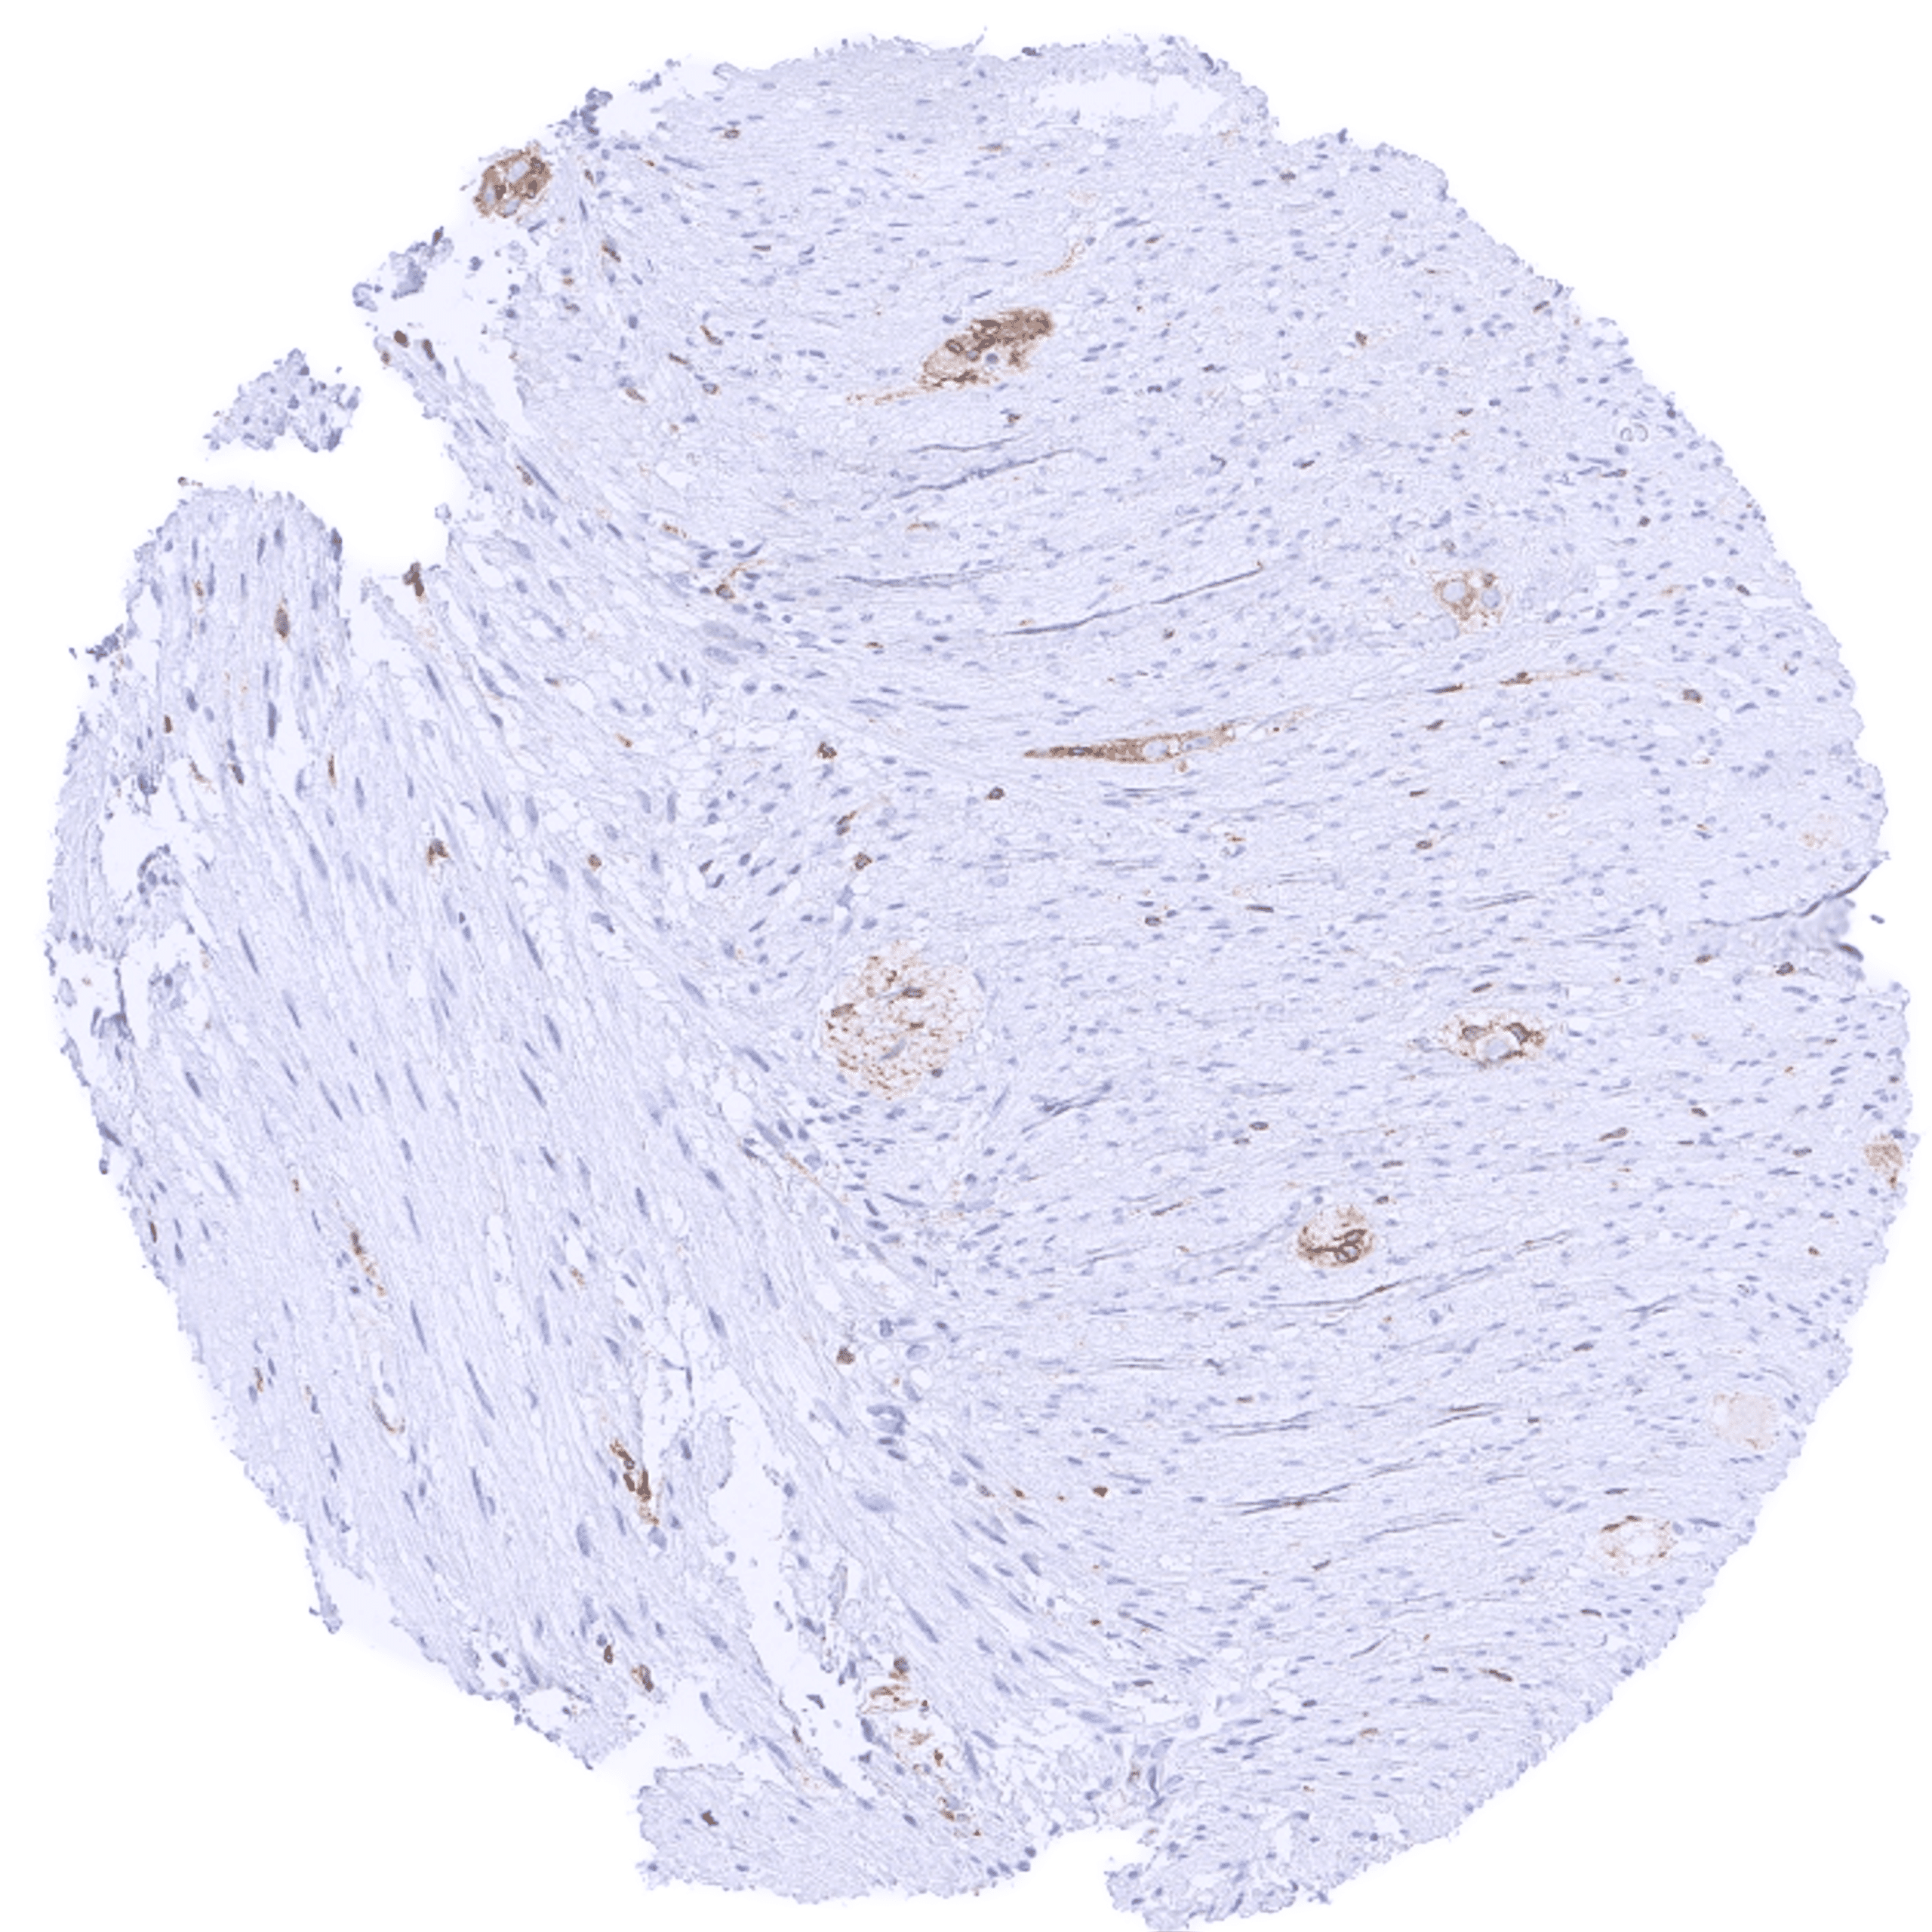

| Uterus, myometrium | Weak to moderate cytoplasmic bcl-2 staining of smooth muscle cells. | |

| Smooth muscle | A faint cytoplasmic bcl-2 staining of muscle fibers can occur in some cases. | |

| Stroma | Negative or faint bcl-2 staining. | |